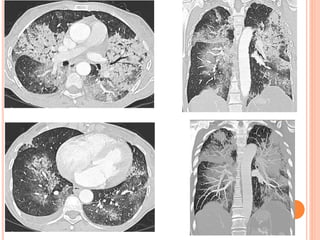

 Imagerie:

 TLX: Infiltrats bilatéraux variables, péri-hilaires.

 TDM: VD +++ et condensations à localisation Images

centrale épargnant la périph. d’HIA

 Parfois asymétriques, rarement unilatéraux.

 Pas d'EPL ni d'ADP.